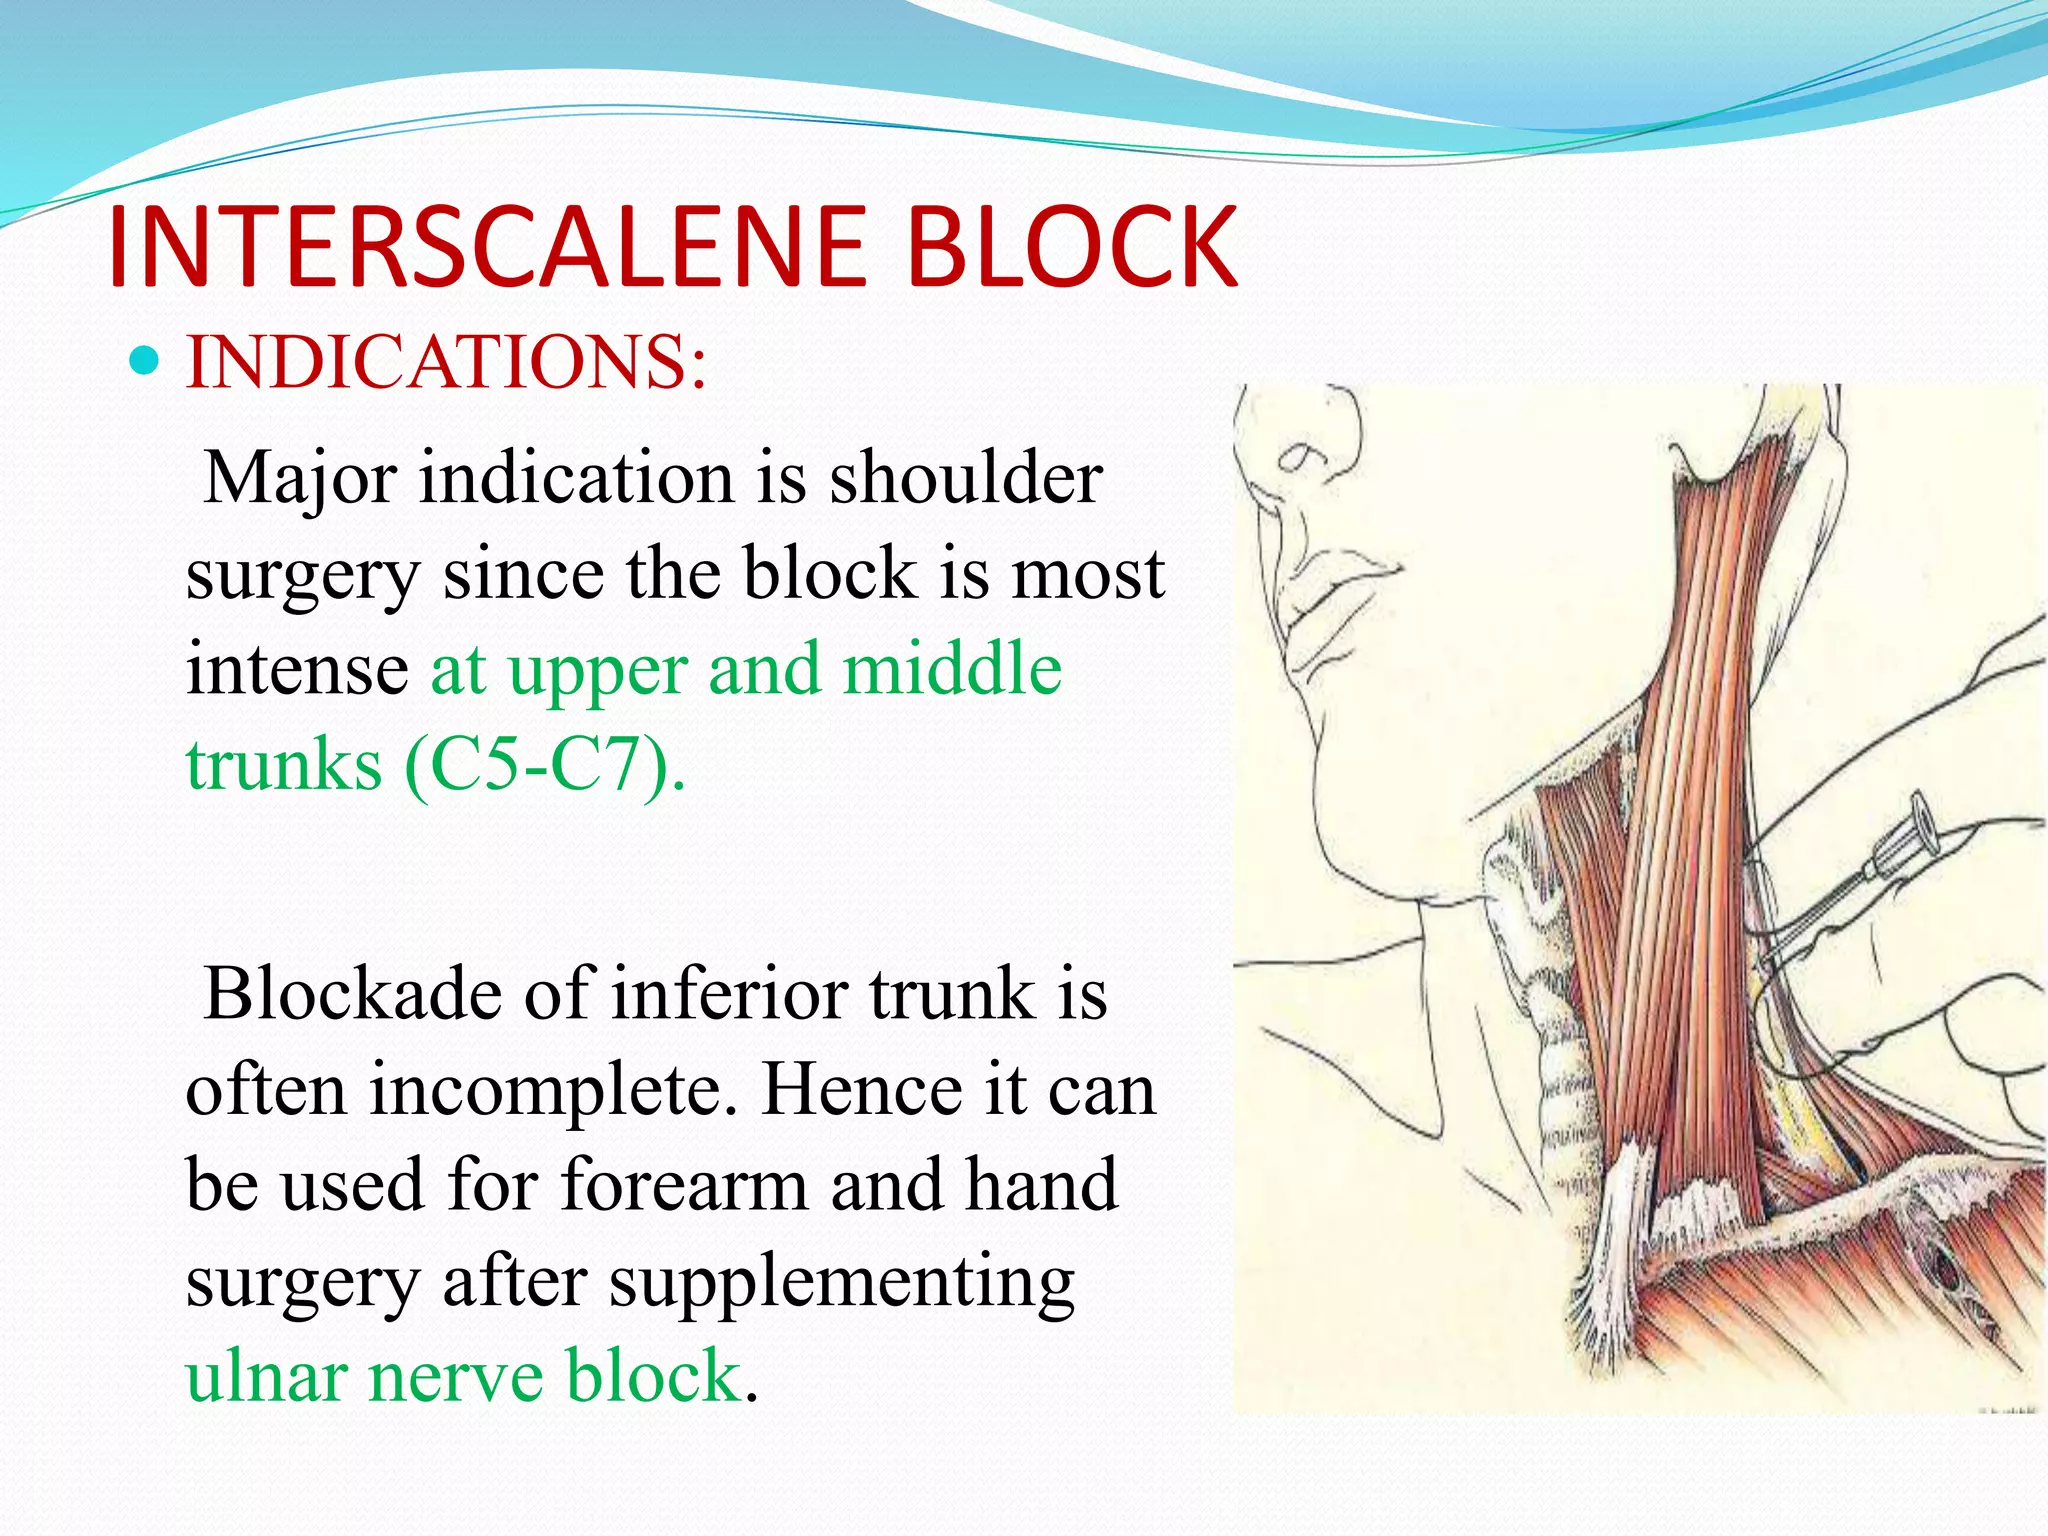

This document provides an overview of brachial plexus anatomy and techniques for brachial plexus nerve blocks. It begins with a description of the brachial plexus formation from cervical and thoracic nerve roots and its branching pattern. Four main approaches for brachial plexus nerve blocks are described: interscalene, supraclavicular, infraclavicular, and axillary. Details are provided on the anatomy and techniques for performing interscalene and supraclavicular brachial plexus blocks. Ultrasound guidance is discussed as an advancement which allows real-time visualization of needle and nerve. Complications are also summarized.